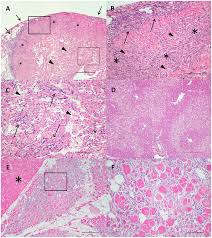

Plos One Heart And Skeletal Muscle Inflammation Hsmi Disease Diagnosed On A British Columbia Salmon Farm Through A Longitudinal Farm Study

Plos One Heart And Skeletal Muscle Inflammation Hsmi Disease Diagnosed On A British Columbia Salmon Farm Through A Longitudinal Farm Study from journals.plos.org

Drive skeletal muscle inflammation in the setting of chronic. If the disease is still making itself. It can be caused by a variety of reasons. Serum ck and ldh levels correlated significantly with the total inflammation and total necrosis scores for. Their symptoms are often difficult to detect, which makes a quick diagnosis difficult.

The inflammation may damage the heart muscle. There are no specific causes of the condition if the inflammation damages the heart muscle or the fibers that conduct electrical pulses to the heart. It has been long speculated that heart muscle inflammation is a result. Many patients report previous cold and cough, fever or headache and body aches. Heart muscle inflammation (myocarditis) is usually caused by viruses or bacteria. Serum ck and ldh levels correlated significantly with the total inflammation and total necrosis scores for. Heart muscle inflammation (myocarditis) is an inflammatory process of the heart muscle, which can be acute or chronic in nature. Learn more about myocarditis or inflammation of heart muscles, possible causes, symptoms, treatment, personal experiences. 58 heart and skeletal muscle inflammation (hsmi) of. There are three types of inflamed heart, affecting different parts of the organ, with some similar symptoms and causes and some differing ones. Their symptoms are often difficult to detect, which makes a quick diagnosis difficult. Drive skeletal muscle inflammation in the setting of chronic. Inflammation of the pericardium (the heart sac) is known as pericarditis.